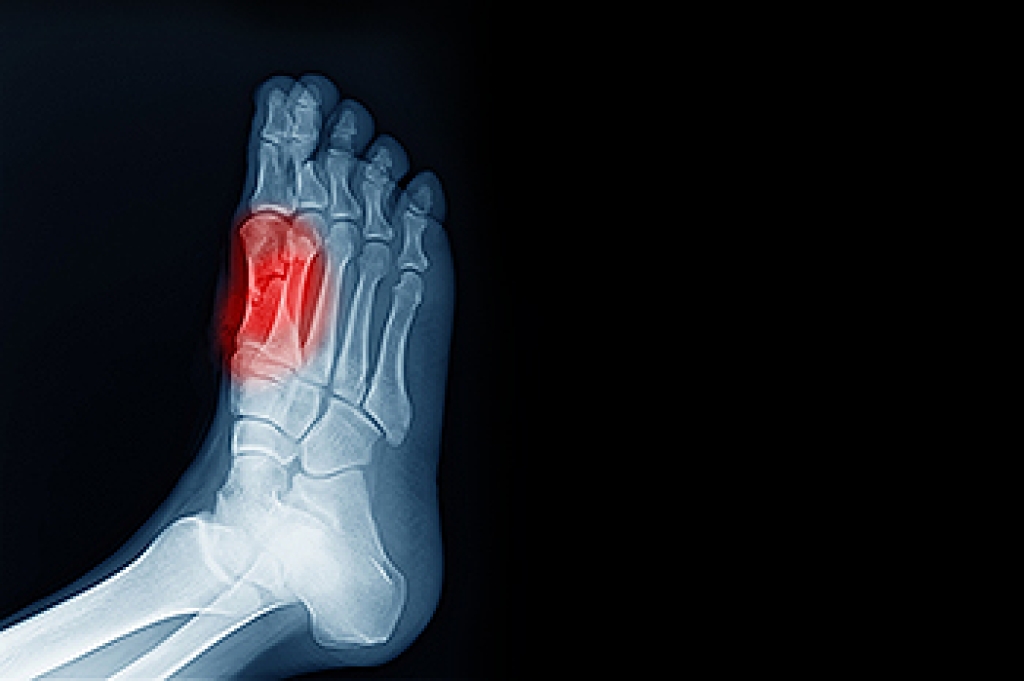

To figure out the cause of foot pain, podiatrists utilize several different methods. This can range from simple visual inspections and sensation tests to X-rays and MRI scans. Prior medical history, family medical history, and any recent physical traumatic events will all be taken into consideration for a proper diagnosis.